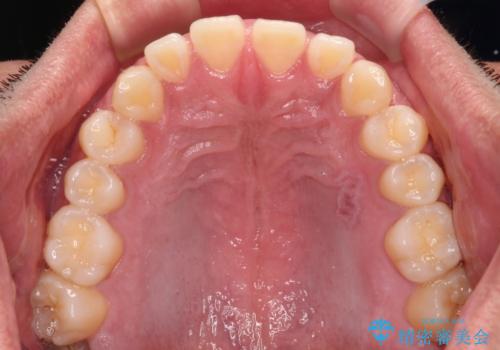

- 上下前歯の隙間を気にして来院された患者様です。

飲み込みや話をするときに舌を突出させる癖が強くあり、それが原因でスペースが空いていました。

舌癖を改善するためのトレーニングを行いながら、ワイヤー装置を用いて前歯の隙間を閉じていくこととしました。

舌のトレーニングをしっかりと行ってくださったおかげで、順調に治療を終えることができました。

舌の突出癖が速やかに改善され、後戻りによるスペースは今のところ認められておりません。